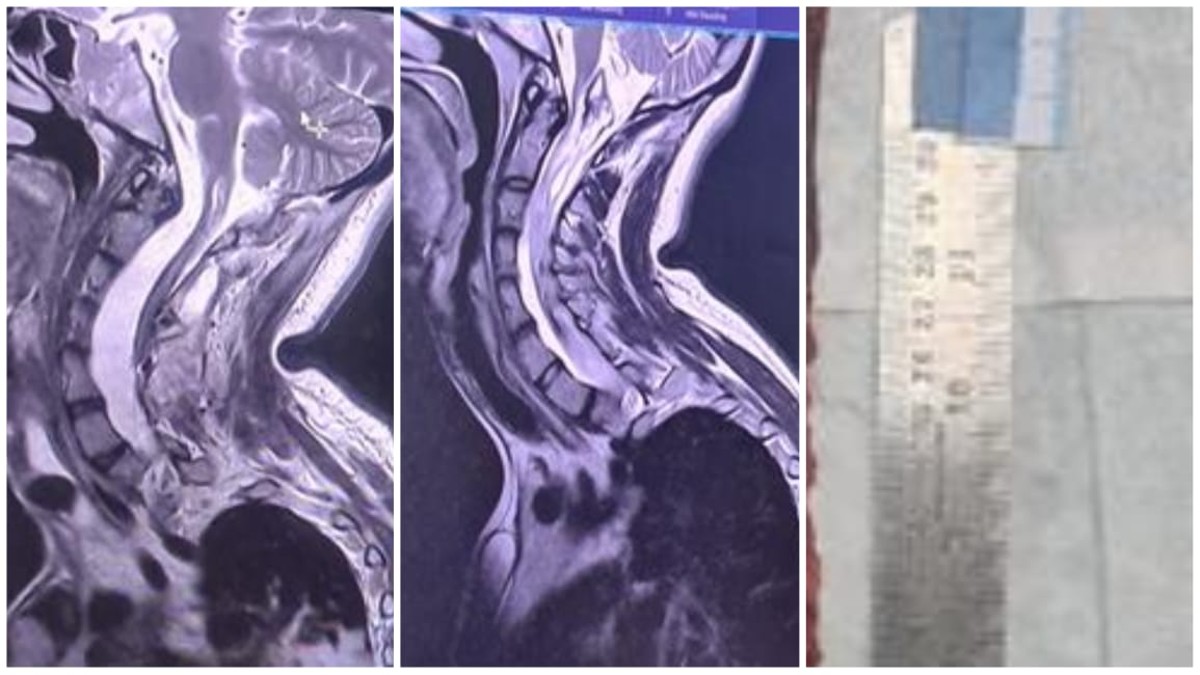

केस का संचालन डॉ सुमित राज ने किया, केस में सहयोग डॉ जितेंद्र और डॉ अभिषेक ने किया। सर्वाइकल से डी12 वर्टिब्रा तक लैमिनोटॉमी की गई। ट्यूमर को पूरी तरह से काट दिया गया और 15 घंटे तक चले ऑपरेशन में मामला ख़त्म हो गया। यह ट्यूमर करीब 40 सेंटीमीटर तक लंबा था। ट्यूमर हटाने के बाद स्पाइन लैमिनोटॉमी को मिनी प्लेट और स्क्रू से ठीक किया गया। न्यूरो ओट स्टाफ का सहयोग अनुकरणीय था, विशेषकर नीनू, भगवती, नंदराम और अन्य का।